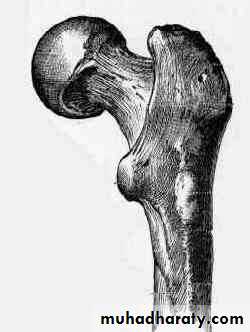

Pathological anatomy and classification

The most useful is that of garden which is based on amount of displacement apparent in the pre-reduction x-ray of the neck femur.

Stage 1

impacted

Stage 2

complete fracture Undisplaced

Stage 3

complete with moderate displacement.

Stage 4

severely displaced fracture.